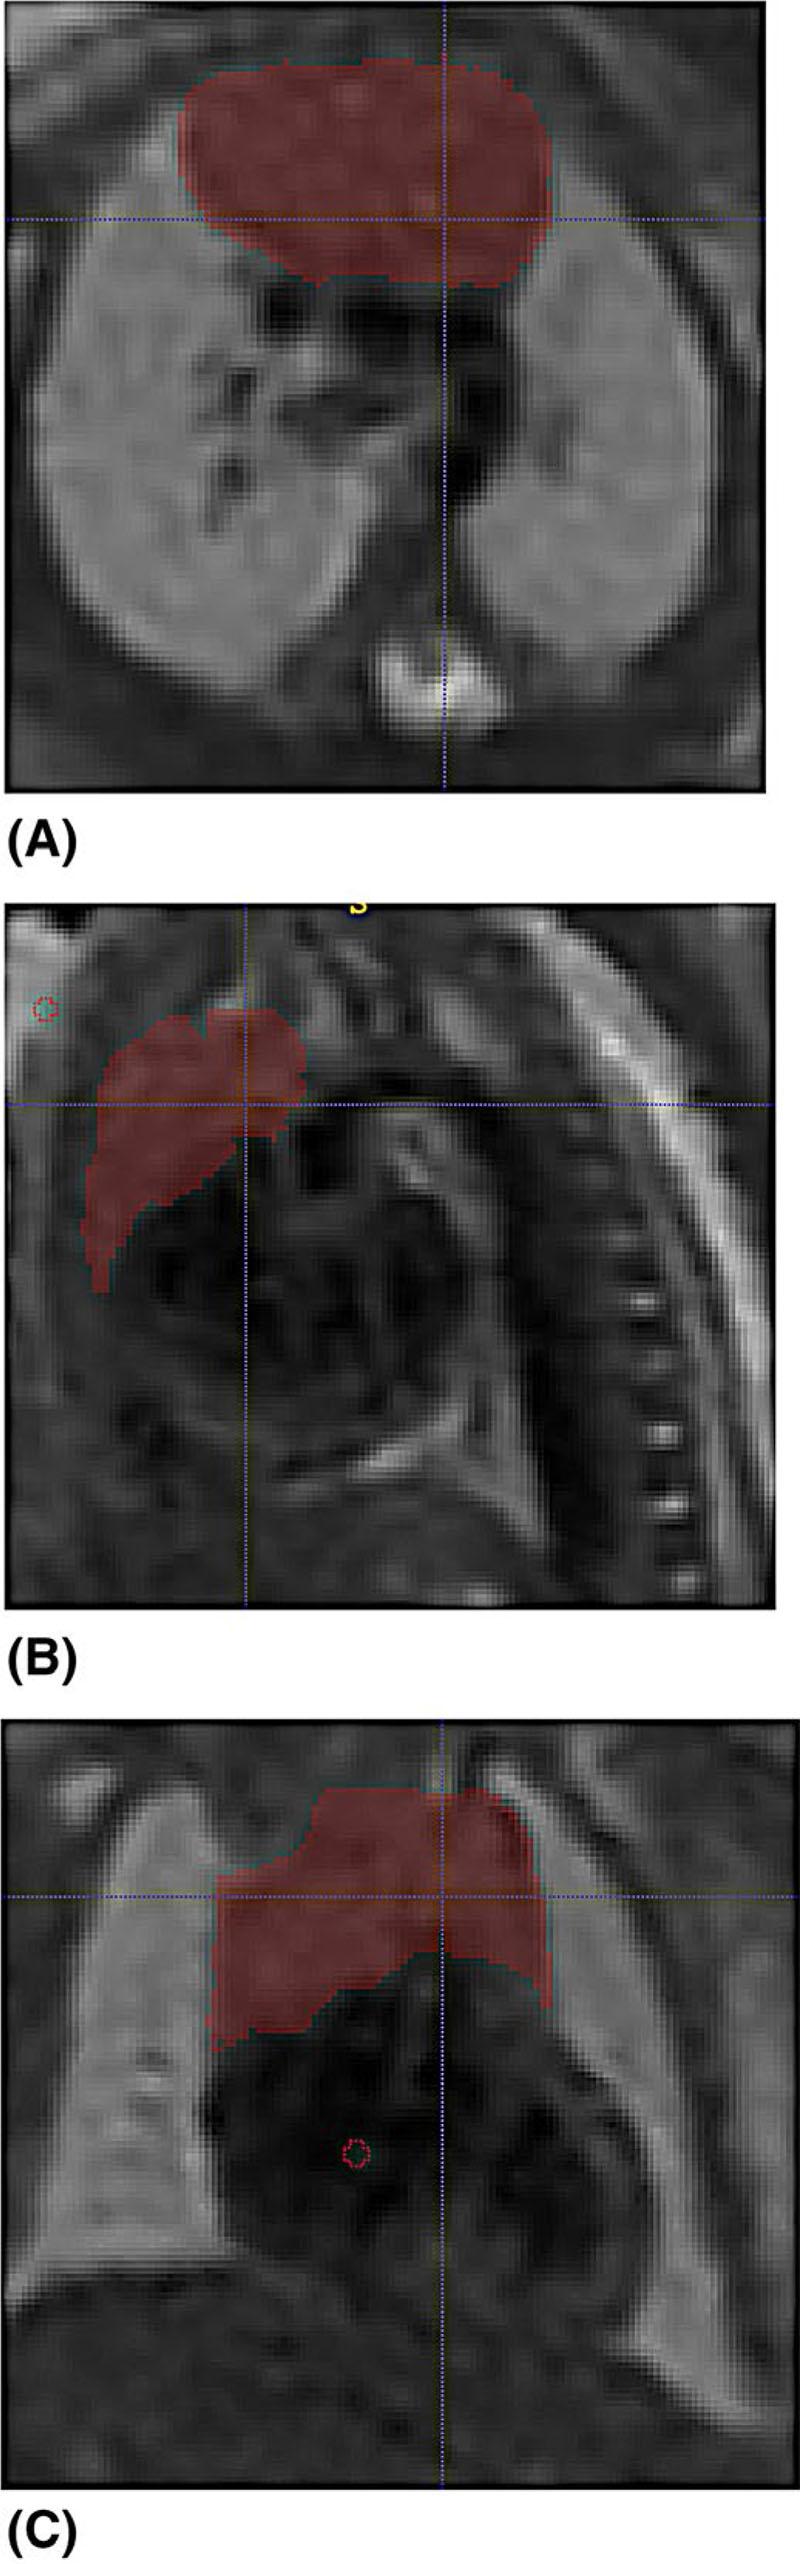

Women at high-risk of preterm birth at 20-32 weeks of gestation were recruited. A control group was obtained from existing data sets acquired as part of three research studies. A fetal MRI was performed on a 1.5T or 3T MRI scanner: T2 weighted images were obtained of the entire uterine content and specifically the fetal thorax. A slice-to-volume registration method was used for reconstruction of three-dimensional images of the thorax. Thymus segmentations were performed manually. Body volumes were calculated by manual segmentation and thymus:body volume ratios were generated. Comparison of groups was performed using multiple regression analysis. Normal ranges were created for thymus volume and thymus:body volume ratios using the control data. Receiver operating curves (ROC) curves were generated for thymus:body volume ratio and gestation-adjusted thymus volume centiles as predictors of preterm birth. Placental histology was analyzed where available from pregnancies that delivered very preterm and the presence of chorioamnionitis/funisitis was noted.

招募了妊娠 20-32 周有早产高危因素的孕妇。对照组来自作为三项研究一部分获得的现有数据集。在 1.5T 或 3T MRI 扫描仪上进行胎儿 MRI:获得整个子宫内容物和胎儿胸部的 T2 加权图像。使用切片到体积配准方法对胸部的三维图像进行重建。手动进行胸腺分割。通过手动分割计算体体积,并生成胸腺:体体积比。使用多元回归分析比较组间差异。使用对照组数据创建胸腺体积和胸腺:体体积比的正常范围。生成胸腺:体体积比和胎龄校正的胸腺体积百分位数作为早产预测指标的接收者操作曲线(ROC)曲线。对非常早产分娩的妊娠进行胎盘组织学分析,并注意绒毛膜羊膜炎/脐带炎的存在。